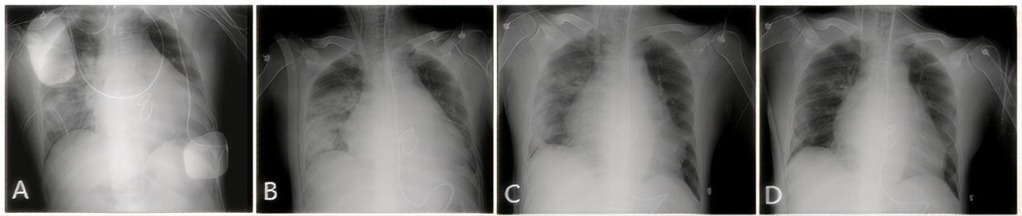

Upon arrival at the intensive care unit (ICU), the patient's oxygen saturation fluctuated between 70% and 90% despite escalation to 100% of inspired oxygen. Arterial blood gas analysis revealed a PaO2 of 59 mmHg. The patient experienced a continuous decline in the oxygenation index (PaO2/FiO2) to <100 mmHg. Large volume of serous secretions were aspirated through the endotracheal tube. The CXR (Figure 1A) revealed partial atelectasis of the left lung and diffuse infiltrates in the right lung, which confirmed the presence of RPE in the right lung. A lung-protective ventilation strategy was immediately instituted, with a target tidal volume of 6 ml/kg, a driving pressure of 16 cmH2O, and a positive end-expiratory pressure (PEEP) of 12 cmH2O. Subsequently, a lung-protective ventilation strategy — with a target tidal volume of 6 ml/kg, driving pressure of 16 cmH2O, and positive end-expiratory pressure (PEEP) of 12 cmH2O — was implemented, along with sedation, muscle relaxation, and diuretic therapy for pulmonary edema. However, the patient's oxygenation failed to improve, and severe respiratory acidosis developed in conjunction with extremely unstable vital signs. The primary postoperative manifestation was refractory hypoxemia. Transthoracic echocardiography was limited by pulmonary edema and air artifacts, precluding a full assessment. However, the limited views available indicated that cardiac function was satisfactory. Following a rapid discussion among a multidisciplinary team comprising cardiothoracic surgery, intensive care, and the ECMO team, the decision was made to initiate VV-ECMO support. A 19Fr cannula was percutaneously inserted into the right internal jugular vein. Additionally, a 23Fr venous cannula was introduced through the common femoral vein to the inferior vena cava and positioned at the right atrium orifice (Figure 3A). VV-ECMO circuit was established via the right internal jugular and right femoral veins at a flow rate of 4.0 L/min with 100% oxygen. Following ECMO initiation, the patient's oxygenation improved rapidly, allowing for a significant reduction in mechanical ventilation parameters to achieve a “lung rest” strategy (FiO2 < 40%, tidal volume 4–6 ml/kg, PEEP 10–12 cmH₂O).

Figure 1. CXR showing the resolution of RPE. (A) Day 1: Extensive opacification throughout the right lung. (B) Day 3: Initial improvement in aeration. (C) Day 10: Marked clearing of the opacification. (D) Day 30 (pre-discharge): Nearly complete resolution.

During his ICU stay, serial assessments—including CXR (Figures 1A–D), lung ultrasounds (Figures 2A–D), computed tomography (CT; Figures 3B,C), and blood gas analyses—were obtained to monitor his condition. The chest CT revealed significant exudation in the right dorsal segment. Based on this finding, prone positioning ventilation (PPV) was initiated as an adjunct to the ongoing VV-ECMO therapy to treat the RPE (Figure 3D). By postoperative day 10, the patient's CXR demonstrated marked improvement and lung auscultation findings were unremarkable, enabling the discontinuation of VV-ECMO. The patient was successfully extubated on postoperative day 12 and was subsequently discharged on postoperative day 30 without sequelae. Transthoracic echocardiography prior to discharge demonstrated normal function of the prosthetic valve. Informed consent was obtained from the patient for the publication of his clinical details and images.